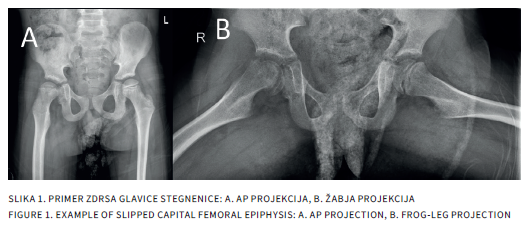

Musculoskeletal pain is one of the most common reasons for pediatric visits. Although the causes are often benign, such as growing pains or overuse syndromes, similar symptoms may also conceal serious orthopedic conditions, including Perthes disease, slipped capital femoral epiphysis, or neoplasms. This article presents the diagnostic approach to children with joint pain and provides a detailed overview of the most frequent orthopedic entities, emphasizing the importance of recognizing red flags and timely collaboration between the pediatrician and the orthopedic surgeon.